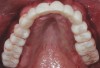

Fig 1. The patient’s initial presentation with healing abutments. (Surgical procedures performed by Mohammad Almogahwi, BDS, and prosthetic procedures performed by the author.)

Figure 1